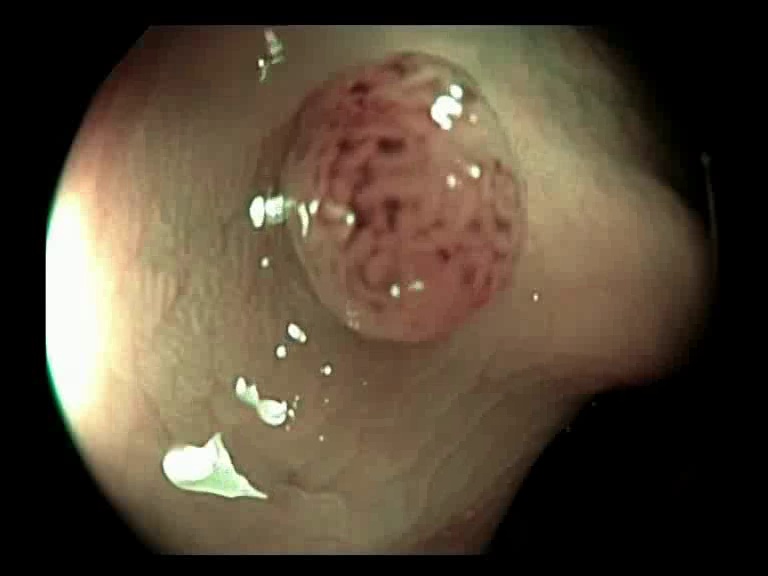

Figure 3: Key-frames obtained by our method and their corresponding depth maps. The polyp is visible from different viewing angles in these selected frames.

The selected key-frames are finally used to reconstruct the 3D surface of the polyp. We have used Facebook’s 3D image GUI to view the reconstructed polyp surface, the link to the video is shown here: https://youtu.be/PJKfk0Mqu2I\href https://youtu.be/PJKfk0Mqu2I. 3D visualization of a polyp helps in surgeries involving the removal of the polyp from its root. This gives better visualization of polyps for diagnosis. Fig. 3 shows some of the results of key-frame extraction and the corresponding depth maps. No publicly available datasets or methods using them that predict depth maps from endoscopic frames exist. Thus, a comparison between different methods for predicting depth from endoscopic images couldn’t be performed.